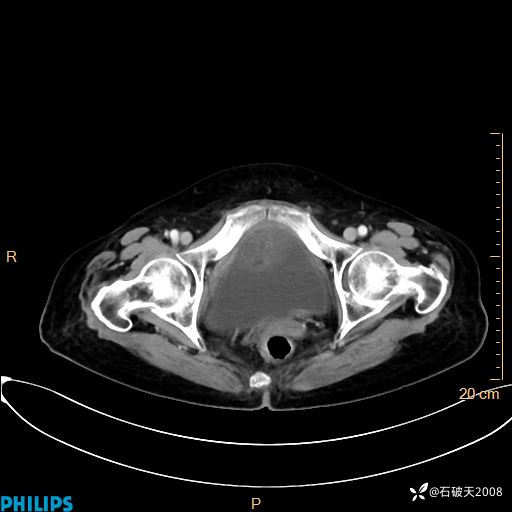

静脉期